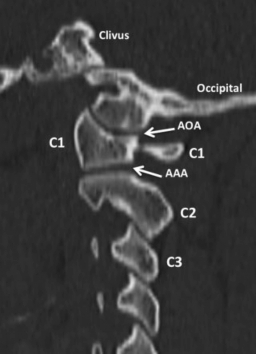

La UCC o charnela cráneo-raquídea está formada por los cóndilos del hueso occipital (CO), la 1ª vértebra cervical o atlas (C1) y la 2ª vértebra cervical o axis (C2). Por eso recibe el nombre de complejo occipito-atloido-axoideo (COAO). Esos 3 huesos están unidos por 5 complejos articulares: ambas articulaciones occipito-atloideas (AOA), la articulación atloido-odontoidea (AAO) y las articulaciones atloido- axoideas (AAA) (►Fig. 1). Por el lado de la base del cráneo es el hueso occipital el que contribuye a la UCC sobre todo por el foramen magno y los CO que se sitúan a sus lados.

TCMD, reconstrucción sagital, ventana ósea. En la vista lateral se visualiza correctamente otra articulación de la UCC, una de las más importantes, la AAO, entre el arco anterior de C1 y la AO de C2. Abreviaciones: AAO, articulación atlanto-odontoidea; AO, apófisis odontoidea; C1, 1ª vértebra cervical; C2, 2ª vértebra cervical; C3, 3ª vértebra cervical.

TCMD, reconstrucción sagital, ventana ósea. En este corte, lateral a la línea media, se identifican las articulaciones que forman parte de la UCC: AOA y AAA. Abreviaciones: C1, 1ª vértebra cervical; C2, 2ª vértebra cervical; C3, 3ª vértebra cervical.